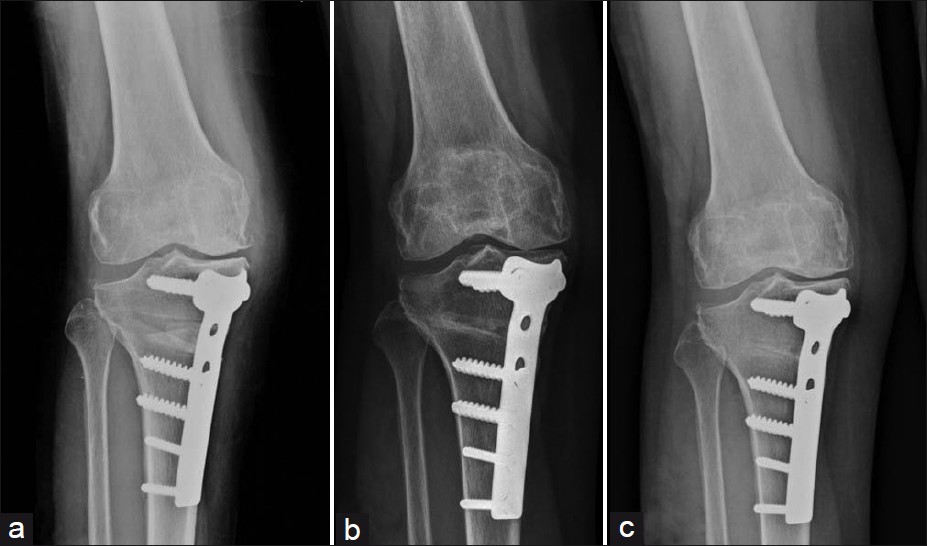

High Tibial Osteotomy is a procedure in which the upper part of the shinbone (tibia) is surgically cut and realigned to shift weight away from the damaged portion of the knee. Plates and screws are used to stabilize the bone during healing. HTO improves knee function, reduces pain, and can help prevent or delay arthritis progression in the affected compartment.